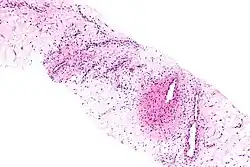

Aggressive angiomyxoma

| Micrograph of an aggressive angiomyxoma. Core biopsy. H&E stain. | |

Angiomyxoma is a myxoid tumor involving the blood vessels.

It can affect the vulva[1] and other parts of the pelvis. The characteristic feature of this tumor is its frequent local recurrence and it is currently regarded as a non-metastasizing benign tumor.[2]

Microscopy

- Vascular appearance of tumor[7]

- Hypocellular mesenchymal lesion

- Spindled and stellate cells with an ill-defined cytoplasm

- Cells loosely scattered in a myxoid stroma

- No evidence of nuclear atypia and mitosis

- Numerous, thin-to-thick wall vessels of different sizes

- Myxoid, hypocellular background

- Bland cytological appearance of spindle cells